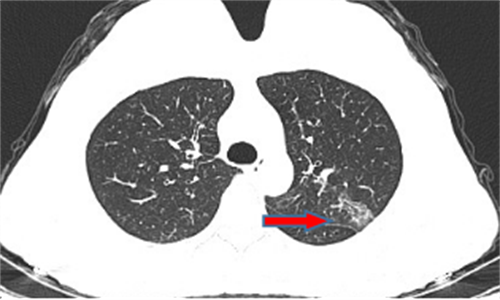

王女士,57岁,体检发现右下肺结节2月,术后病理诊断肺结节为肺隐球菌病。

李先生,45岁,发现右上肺结节2年,近期长大,术后病理诊断肺结节为炎性假瘤。

龙先生,65岁,体检发现右下肺结节,术后病理诊断肺结节为硬化性血管瘤。

郭女士,63岁,体检发现右下肺结节20天,术后病理诊断肺结节为浸润性腺癌。

王女士,65岁,体检发现右上肺磨玻璃结节16天,术后病理诊断肺结节为浸润性腺癌。

王女士,52岁,体检发现右上肺磨玻璃结节7月,术后病理诊断肺结节为原位腺癌。

王女士,35岁,新冠核酸检查阳性7天,胸部CT检查左上肺磨玻璃影,考虑新冠病毒性肺炎。